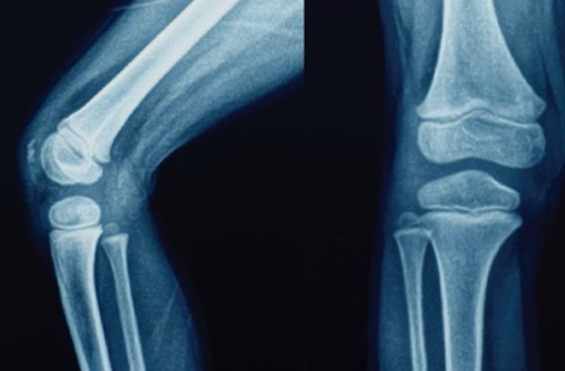

관절은 평생 사용이 되기 때문에 한번 손상이 되면 아주 많은 고생을 하게 되는 만큼

관절 건강은 매번 강조해도 나쁘지 않는 것 같아요~

보스웰리아는 관절 연골 건강 개선에 도움을 줄 수 있음의 기능성과 안전성을 인정받은 건강 기능성 원료로

인도 인디라 간디 의과대학 연구팀에서 보스웰리아 효능에 연구를 해였는데 그 결과

관절염 환자의 관절기능이 83% 개선이 되고 통증이 감소되는 효능을 보였다고 해요~

30명의 관절염 환자가 8주간 진행 된 연구실험에서 보듯이 보스웰리아 효능은 관절염에 아주 특효 한 것이 사실~